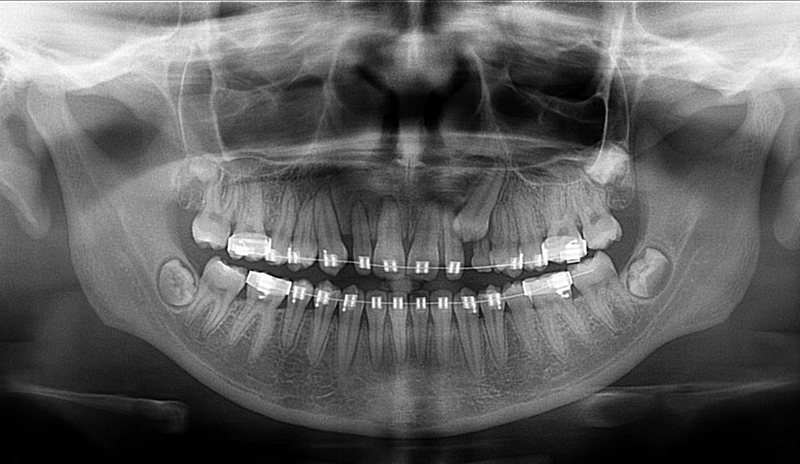

Vyšetření pomocí tohoto přístroje a získaná data používáme

pro každou implantaci, dále ve stomatochirurgii (zlomeniny čelistí, zuby moudrosti, cysty, onemocnění čelistního kloubu), ortodoncii (retinované zuby, nadpočetné zuby), parodontologii atd.

Lékař si vytvoří všechny typy zobrazení potřebných pro naplánování – tedy 2D snímky (panoramatický), příčné řezy i 3D model.

Vidí zde i důležité anatomické útvary – čelistní dutinu, průběh nervu atd. Po proměření množství kosti – šířky i výšky vybere z databáze vhodný typ implantátu a umístí ho do požadované lokality.